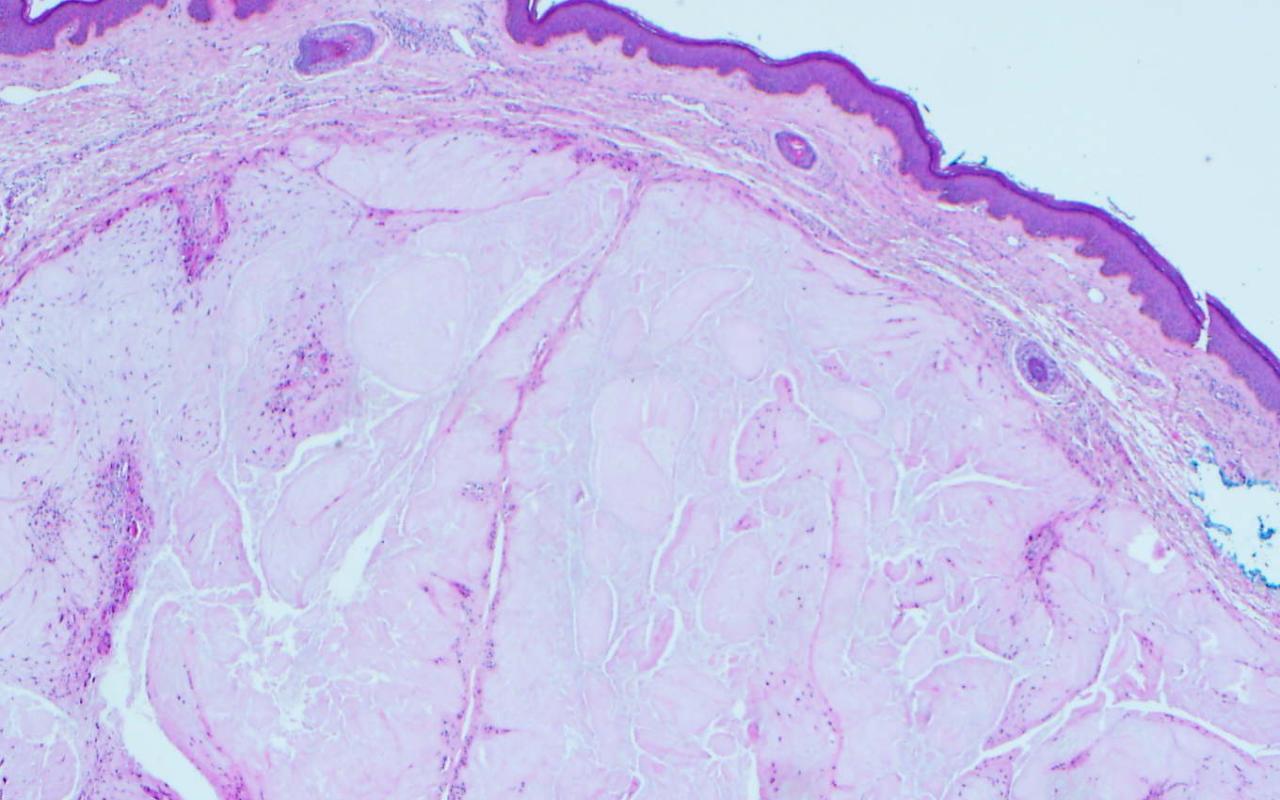

1. A 60-year-old man presents with a poorly demarcated, symmetric, very painful patches of erythema and retiform purpura favoring the buttocks. Bullae and a dusky gray discoloration developed and ulcerations appeared with a black, leathery eschar. Upon palpation there is a surrounding subcutaneous induration that extends beyond the margins of the visibly active lesions. You perform a skin biopsy (see image). Which of the following is the most likely diagnosis?

Correct choice: A. Calciphylaxis

Explanation: calciphylaxis is characterized by intimal fibrosis and medial vascular calcification (that can become transmural) as well as transdifferentiation of vascular smooth muscle cells into osteoblast-like cells; these changes plus thrombosis lead to ischemic necrosis of the skin and soft tissues. Early lesions usually present as poorly demarcated, often symmetric, very painful patches of erythema or retiform purpura. They favor areas with abundant adipose tissue or sites of trauma. Bullae or a dusky gray color may then develop, signifying imminent tissue necrosis and the appearance of ulcerations with black, leathery eschars. Often there is surrounding subcutaneous induration that extends beyond the margins of the visibly active lesions and this can be helpful in distinguishing calciphylaxis from other forms of retiform purpura.